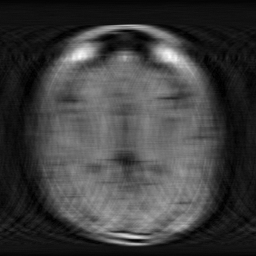

Drag the slider to reveal how our AI reconstructs high-quality low-field images from undersampled k-space

M4Raw dataset